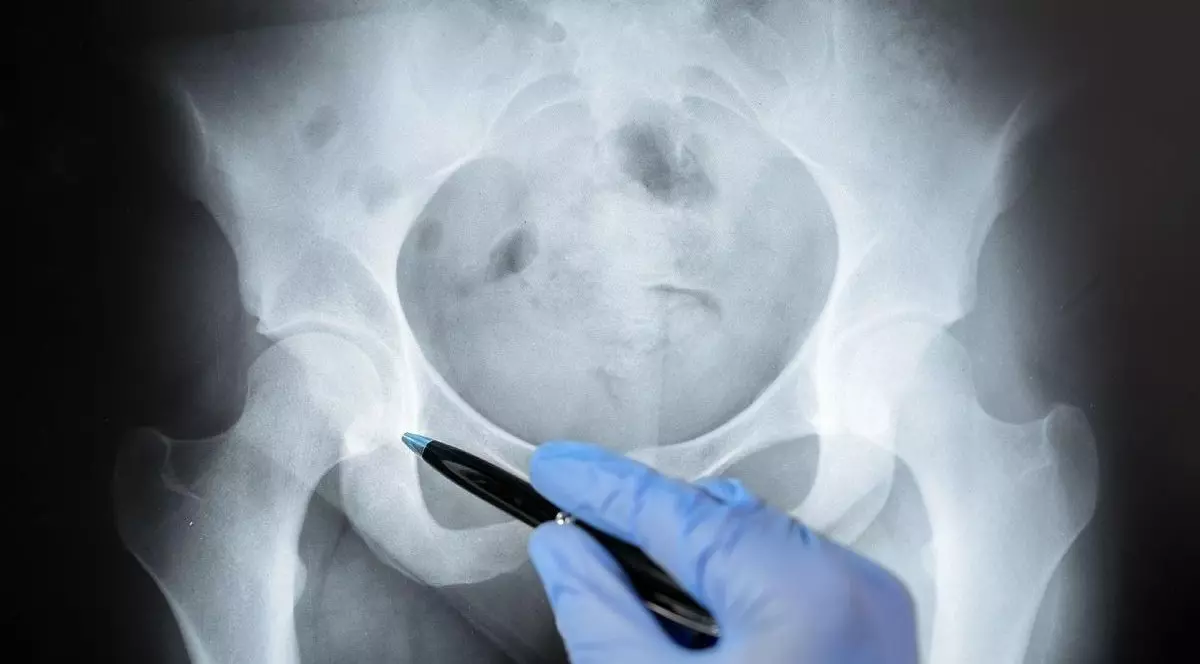

Durerea pelvină cronică este o afecțiune care poate afecta viața de zi cu zi, relațiile personale și starea psihică a pacientului. Cauzele pot fi multiple: de la endometrioză profundă, compresii nervoase sau traumatisme, până la probleme de ordin neurologic care sunt, de cele mai multe ori, tratate superficial sau greșit.

Cum se face diagnosticarea și ce afecțiuni sunt tratate

Pentru a identifica exact sursa durerii, echipa medicală face o evaluare detaliată care include:

- consulturi clinice

- RMN pelvin cu protocol neurovascular

- ecografii Doppler

- teste neurofiziologice și urodinamice

Printre afecțiunile tratate se numără:

- nevralgia de nerv pudendal

- endometrioza cu afectare nervoasă

- compresiile nervilor pelvini

- sindromul de congestie pelvină

- coccidinia neuropată

- disfuncții urinare, intestinale și sexuale cu cauze neurologice